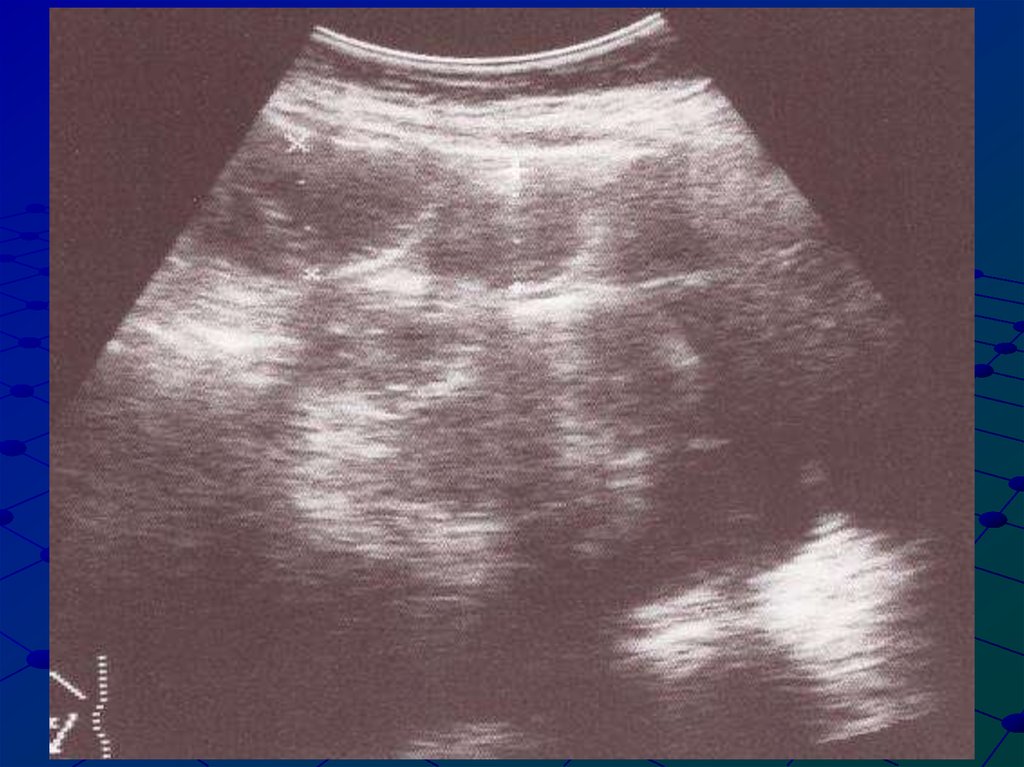

23. Ультразвуковые признаки динамической тонкокишечной непроходимости

Расширение просвета тонкой кишки 2-4 см в

диаметре

Наличие жидкостного содержимого и газа в

просвете тонкой кишки

Толщина стенок 2-3 мм

Сглаженность складок тощей кишки

Перистальтика тонкой кишки ослаблена или

отсутствует

Наличие газа в толстой кишке